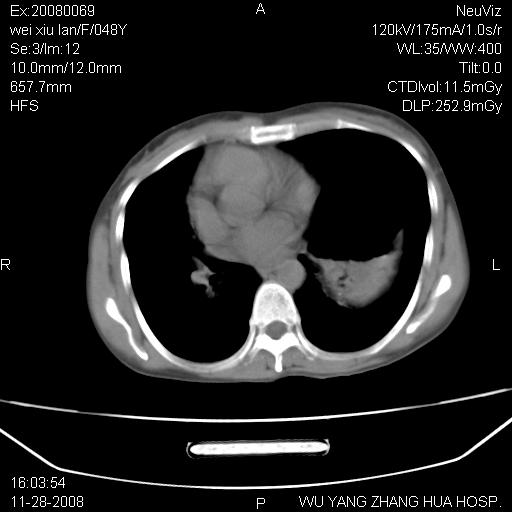

标题: CT16847:女,48岁,咳嗽,发热两日,平常偶有上腹部不适。 [打印本页]

标题: CT16847:女,48岁,咳嗽,发热两日,平常偶有上腹部不适。

能否考虑食管裂孔疝?请老师们多多指教。

胃、脾脏及部分肠管明显升高,并压迫心脏移位,

首先考虑:左侧膈疝。

左侧胸腔内见胃肠及脾脏影

支持膈疝

这个是左侧膈膨升伴不完全性胃翻转,手术将松弛的左横膈膜折叠缝合即解决问题。

支持左侧膈疝,心脏受压右移.

左下肺不张、膈膨升,胸腔胃

左膈顶及肋膈角均上移,膈面光滑,考虑左膈肌麻痹